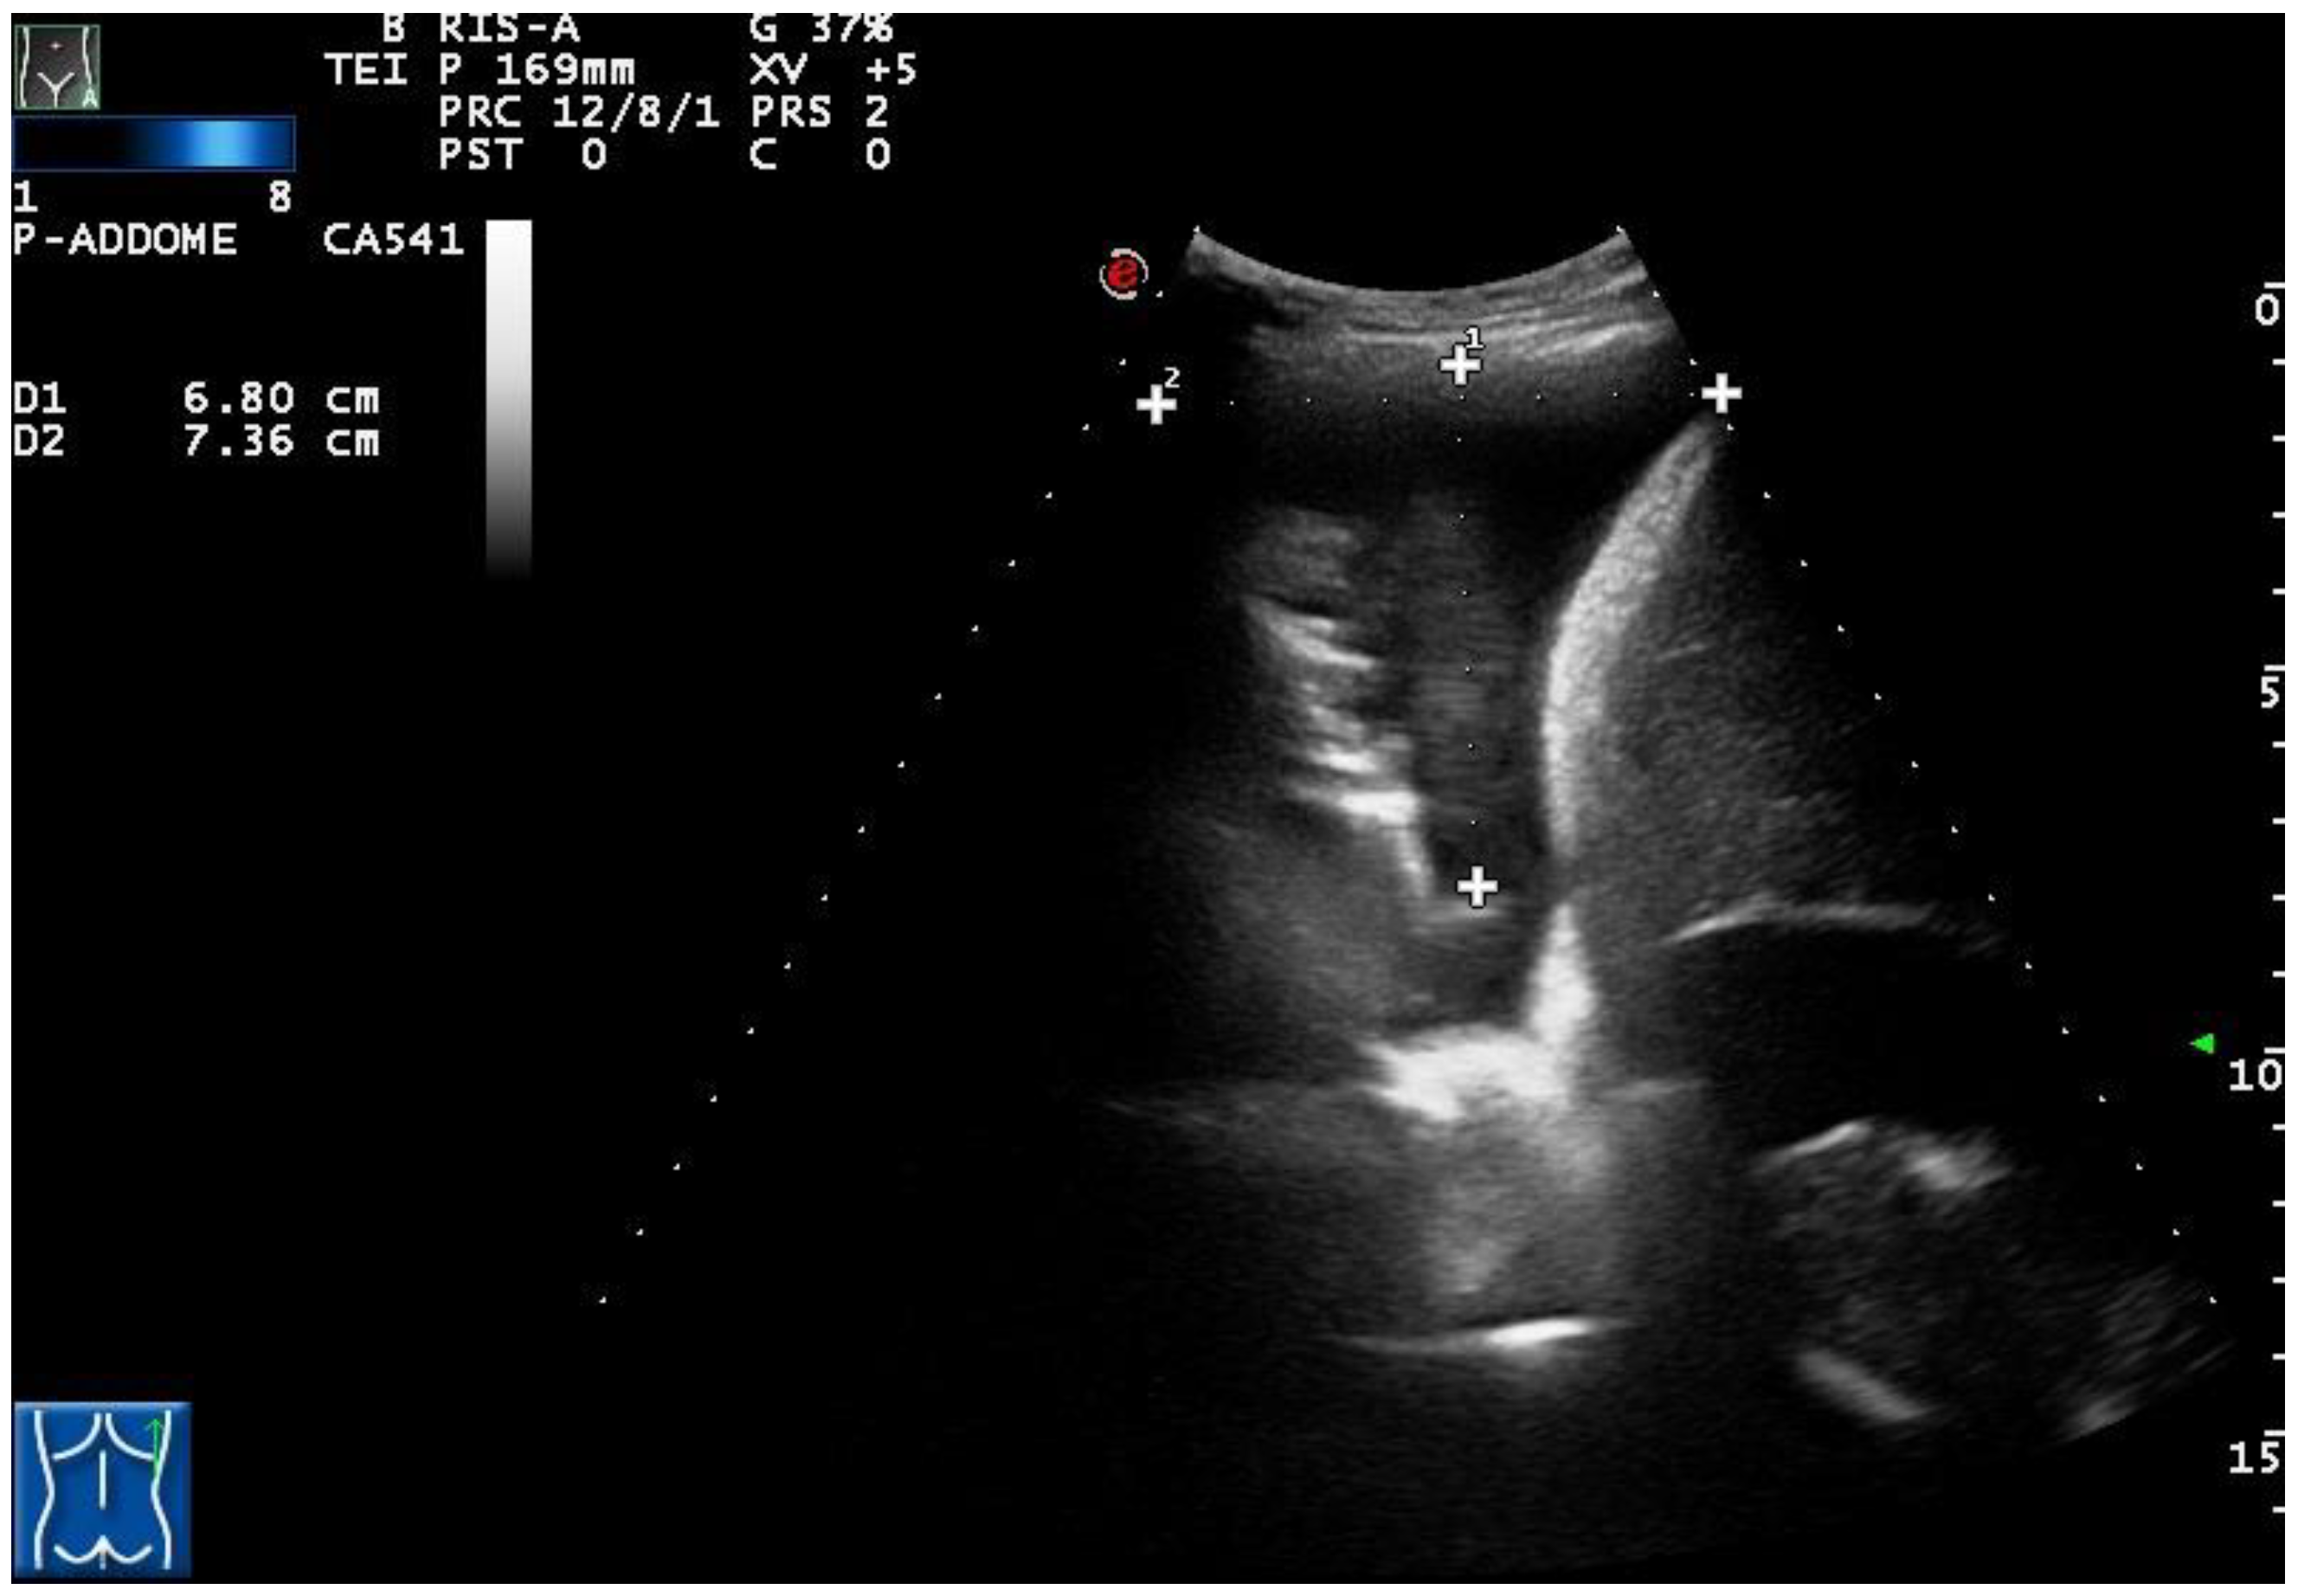

Figure 4. (A) TUS scan showing a homogeneous iperechoic pleural exudates viewed by a convex multifrequency probe (3.5 MHz). The drained fluid was macroscopically hemorrhagic. (B) The corresponding CT scan shows a large right effusion in a patient with a diagnosis of metastatic kidney cancer.

Twenty out of 22 homogeneous hyperechoic effusions (90.91%) were macroscopically hemorrhagic (Figure 4).